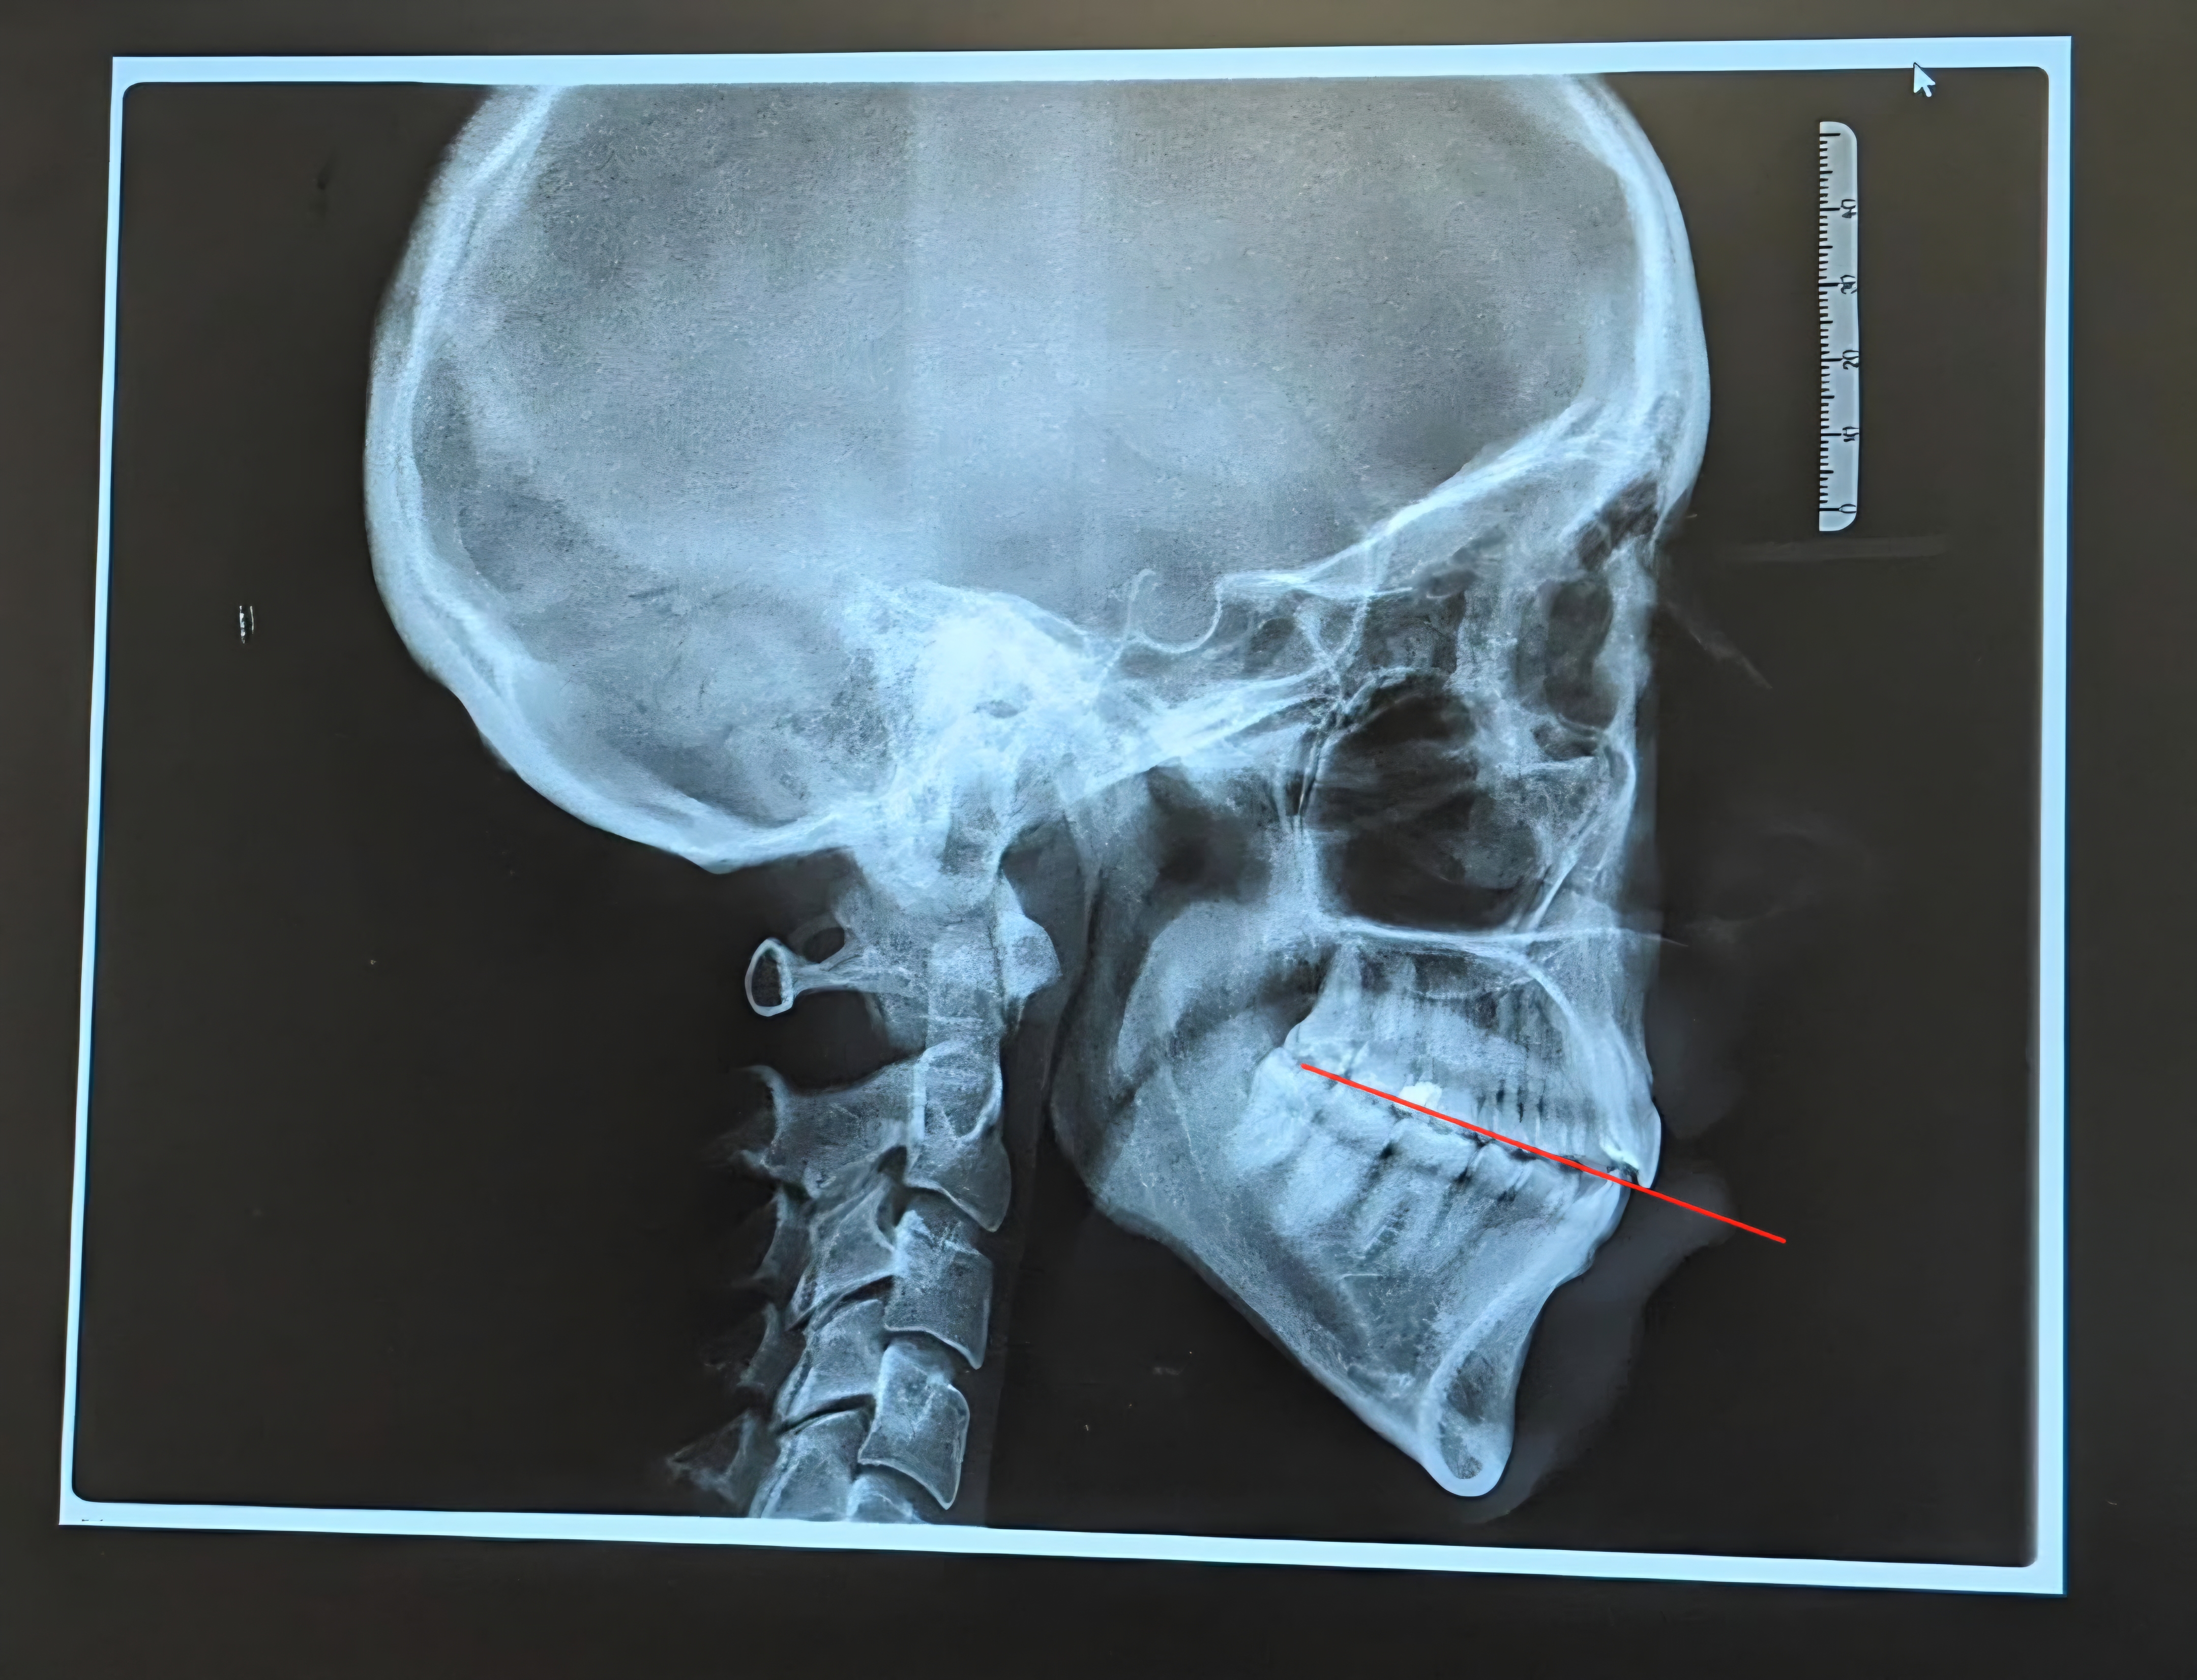

Here the Occlusal plane is better but this person is still downgrown - this is optimal